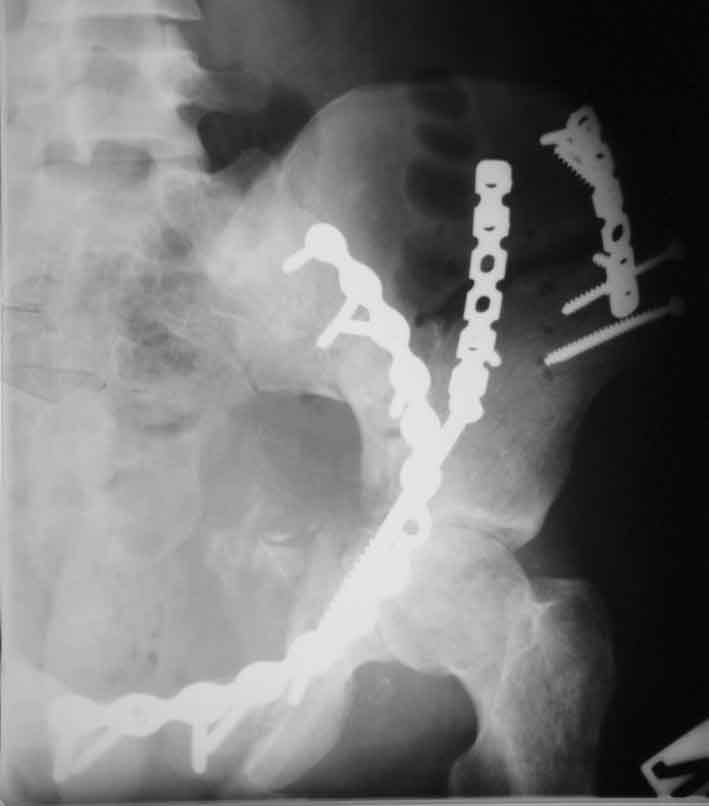

[Ortho] Рентгенограммы после операции

Подвздошная